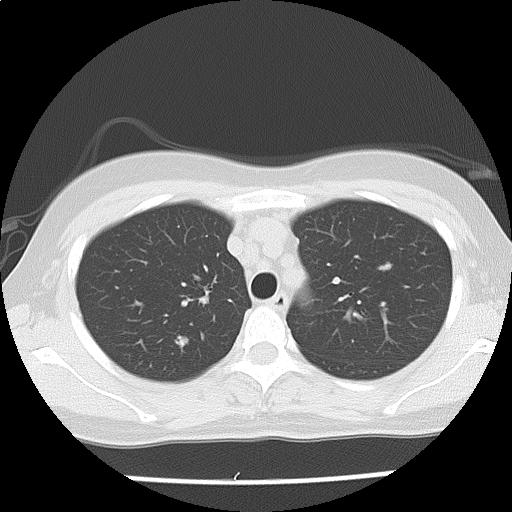

両肺に径数 mm~約9 mm の結節が多発しており(添付画像以外にも認める)、辺縁不整を認める。

多発肺転移の可能性をまず除外する必要があり、原発としては乳癌、膵癌などと考える。

悪性が否定的な場合には、感染症、血管炎、サルコイドーシスなども鑑別に挙げられる。

縦隔リンパ節を散見する。胸水は認めない。

多発肺結節・縦隔リンパ節腫大:r/o 多発肺転移